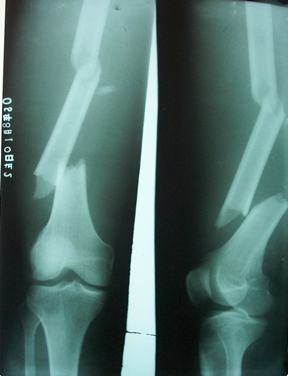

燕化医院开展手术治疗四肢、骨盆骨折患者取得了良好的效果。股骨颈骨折一般以全髋关节置换(THA)和半髋关节置换为主;而对于股骨转子间骨折的外科治疗多采用内固定手术,包括锁定钢板;动力髋系统即DHS、PFN(A)。具有创伤小(微创)、内固定牢固、术后恢复快便于提早下地活动等优点。肱骨、尺桡骨、股骨干、胫骨干的骨折主要采用带锁髓内钉和锁定钢板治疗;复杂的骨盆骨折则采用切开复位,重建钢板治疗。

图5. 股骨干多段骨折